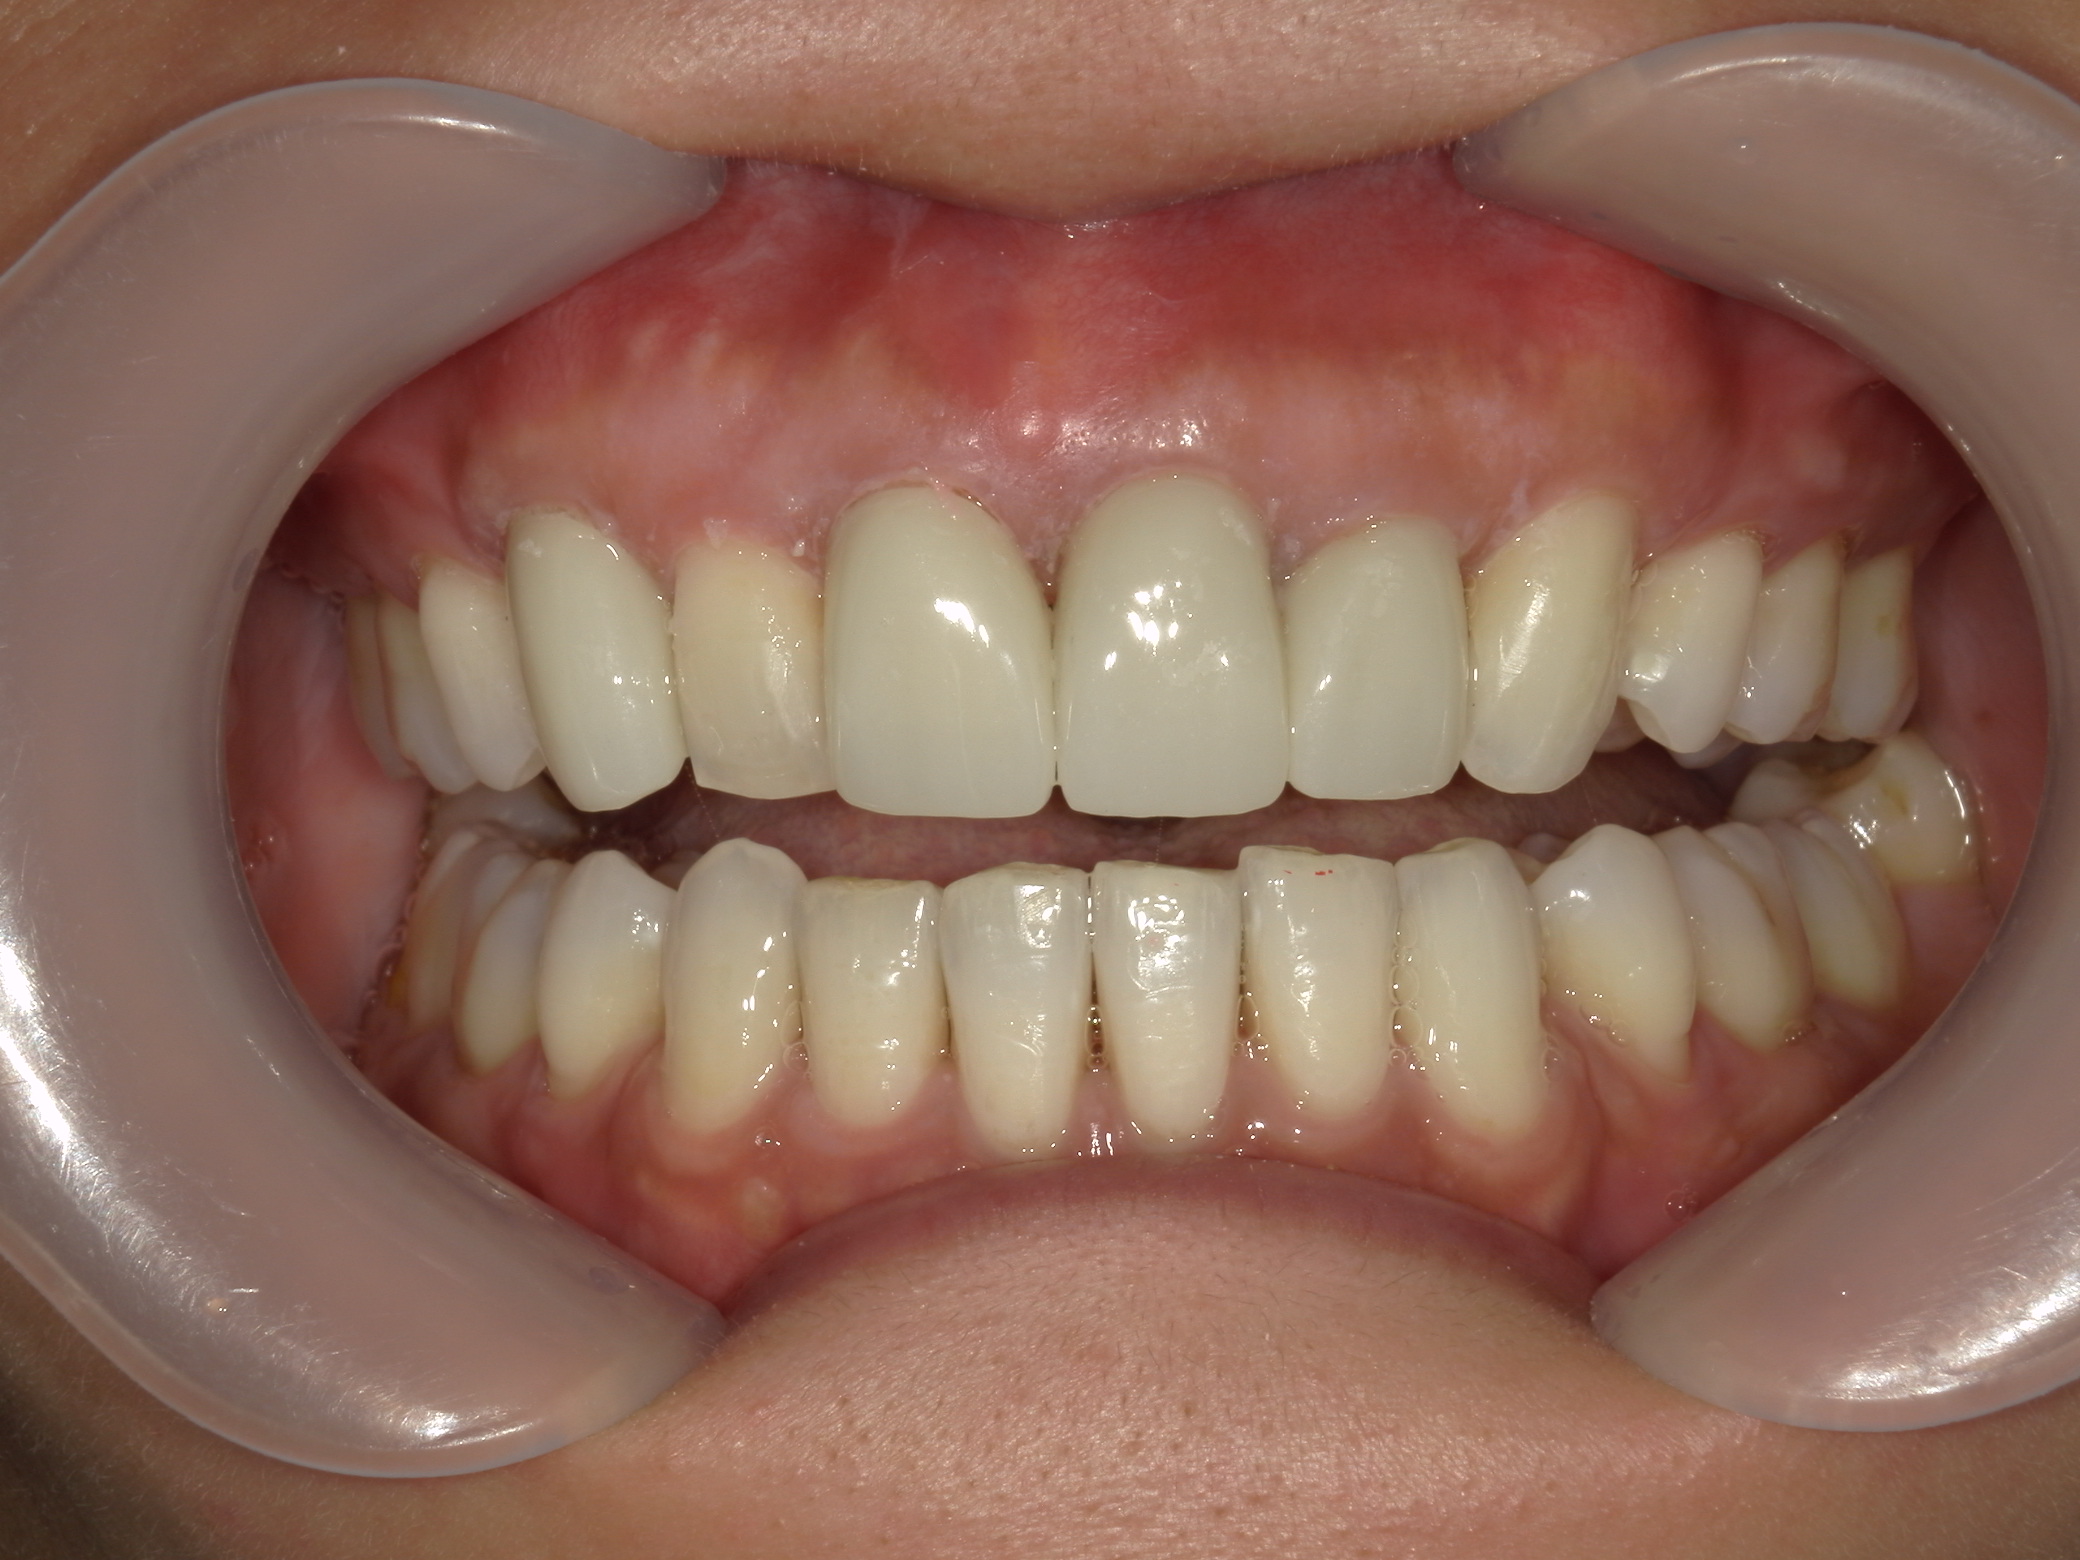

全顎ワイヤー矯正 症例(82)

主訴: 前歯の歯並びが気になる。

上下左右 第一小臼歯(4本)、左右上 親不知(2本)を抜歯。

ミニインプラント、アップライトスプリングを併用。

矯正前に左右上前歯4本を仮歯に変え、矯正治療後にセラミック(SHT)に冠せなおしました。

カテゴリー : ガタガタ(叢生)